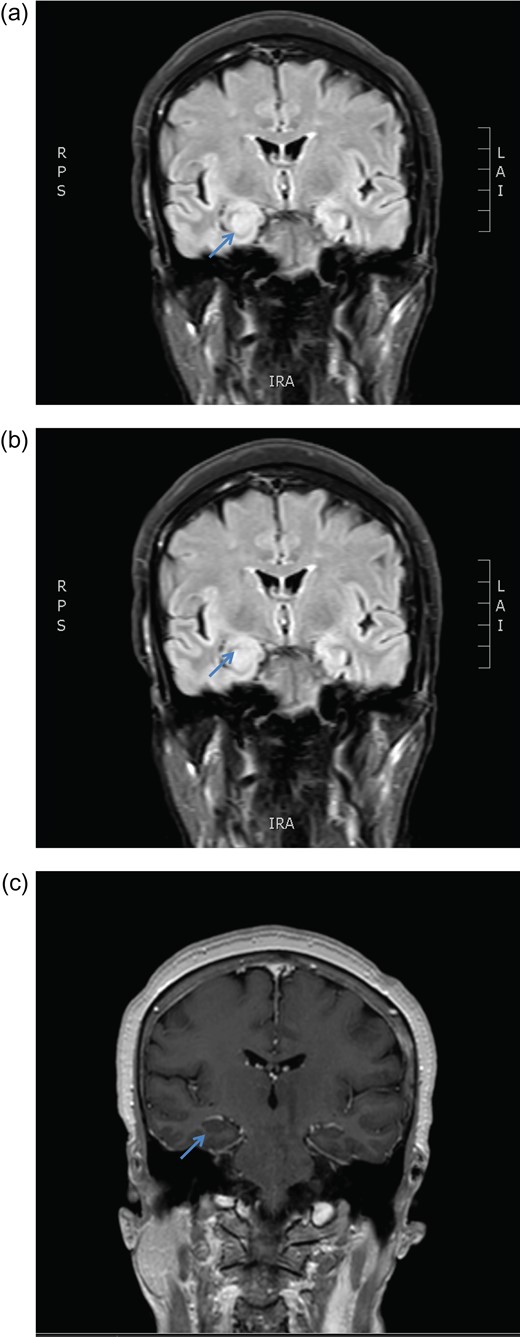

November 2015, she had another seizure episode and MRI brain at that time was suspicious for a right mesial temporal lobe low-grade glioma (Fig. 1). She had no pre-seizure personality changes, hearing difficulty or family history of either seizure disorder or brain or any other tumour. Her neurological screening examination was unremarkable.

MRI brain coronal T2 FLAIR sequence depicting persistent right hippocampal high signal change in January (a) and March (b) 2016. There is no enhancement post gadolinium injection (c).

December 2015, she had a normal electroencephalogram (EEG). Subsequent MRI done January and March 2016 showed T2 Weighted Imaging Fluid Attenuated Inversion Recovery (T2WI/FLAIR) changes in the right medial temporal lobe (Fig. 2). Right hippocampal signal change was suspicious of low-grade glioma with a differential diagnosis of post viral limbic encephalitis. There was no enhancement with intravenous gadolinium administration and no other suggestion of a focal malignant disease. She remained clinically well and repeat MRI done October 2016 showed areas of signal abnormalities focused around the posterior horns of the lateral ventricles and but no sign of right temporal lobe low-grade glioma or encephalitis (Fig. 3). All of these signal changes resolved completely with repeated MRI and she had no further seizures.